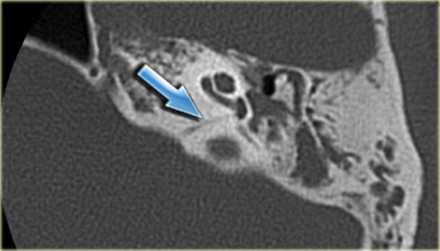

Происходящие при отосклерозе изменения костной ткани капсулы лабиринта иногда определяются по результатам прицельной рентгенографии черепа. Однако более информативным исследованием является КТ черепа, позволяющая визуализировать очаги отосклероза.

КТ височных костей. С обеих сторон диффузное снижение пневматизации ячеек сосцевидного отростка и пирамиды височной кости за счет отосклероза